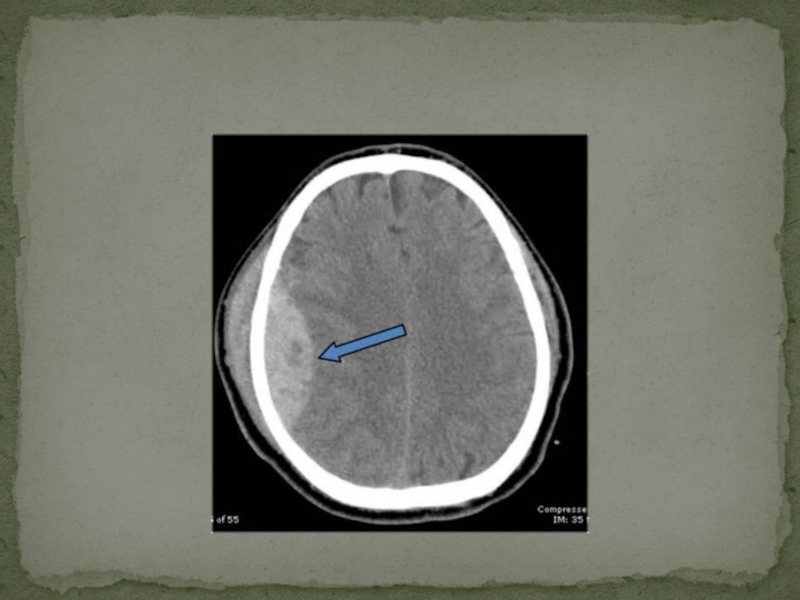

Слайд 37Компьютерная томография. Магнитно-резонансная томография

При острой субдуральной гематоме выявляется серповидная зона

гомогенного повышения плотности.